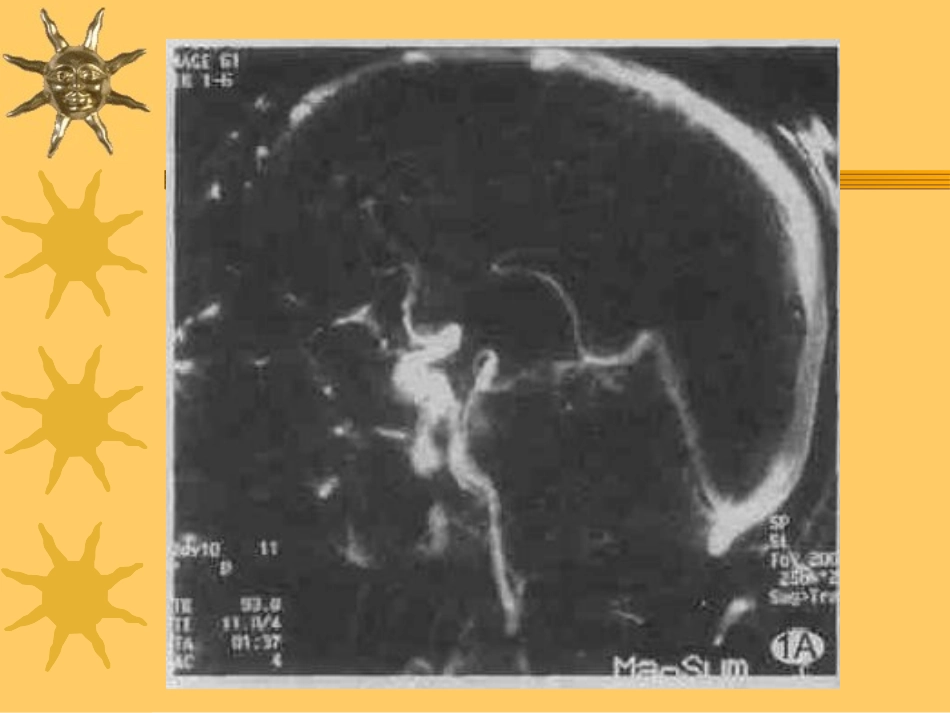

颅内静脉窦血栓形成(cerebralvenousthrombosis,CVT)颅内静脉窦的解剖颅内静脉窦-上矢状窦、下矢状窦、直窦、横窦、乙状窦和海绵窦。CVT的解剖基础–无瓣膜,静脉血可以发生逆流;–颅内、外静脉间有丰富的吻合支–部分颅内静脉堵塞可不出现临床症状。上矢状窦内流速缓慢、迂曲、回旋,易于形成血栓。临床特点发病率:综合文献,CVST约占全部脑血栓形成的3.5%。青壮年多见,男/女=13∶。急性、亚急性或慢性发病,亚急性常见。主要的临床表现–(1)进行性无缓解的头痛呕吐-最常见–(2)眼底乳头水肿等高颅压症状–(3)癫痫:常见于上矢状窦血栓或脑表浅静脉血栓。–(4)不同程度的意识障碍及精神症状,多由于高颅压或深静脉血栓累及双侧丘脑所致。临床特点–(5)局灶性神经功能缺损,最常见的是运动和感觉障碍,通常为单瘫、轻偏瘫,以下肢为主,也可出现双下肢瘫,酷似脊髓病变。–(6)其它症状和体征颅神经麻痹、失语和小脑体征,如Ⅲ、Ⅳ、Ⅵ颅神经麻痹提示海绵窦血栓,Ⅸ、Ⅹ颅神经麻痹提示颈内静脉血栓,Ⅴ、Ⅵ颅神经麻痹形成的岩尖综合征提示岩下窦血栓,多继发于中耳炎诊断规律(1)年龄范围相对固定,多为青年(2)病前身体素质较好,上呼吸道感染、劳累及饮酒等可诱发(3)多为急性起病,病情逐渐进展(4)首发症状主要为头痛伴呕吐(特别是喷射状呕吐)及视乳头水肿,伴或不伴局灶性神经功能缺损及癫痫发作,也可以视力障碍、肢体无力或精神异常起病。鉴别:中枢神经系统感染、肿瘤和非高血压性出血、脑膜癌病。病因各种原因及疾病引起的高凝状态–(1)妊娠和产褥期–(2)口服避孕药–(3)遗传性抗凝和纤溶系统异常疾病–(4)炎症性肠病,如Crohn病和溃疡性结肠炎–(5)血液系统疾病–(6)全身性疾病,如恶性肿瘤、肾病综合征、系统性红斑狼疮、血栓闭塞性脉管炎、Behcet综合征等–(7)全身及局部感染,如败血症、鼻窦炎、中耳炎等–(8)其它,如头外伤,严重脱水、疲劳、消耗性疾病等。预后病情凶险、病死率高、预后不良。70%可完全康复,11%遗留残疾或后遗症,19%导致死亡。与昏迷程度、年龄、局限性神经系统体征和迅速发展的颅内高压等因素有关。就病因而言,感染性患者恢复差、病死率高从解剖结构上来讲,脑深静脉和直窦血栓比脑浅静脉和其他静脉窦血栓者预后差。病理(1)脑水肿是脑CVT突出的病理特征(2)出血性梗死是CVT常见的病理改变,特别是上矢状窦血栓合并大脑浅静脉血栓时易出现出血性梗死(3)脑深静脉血栓时,由于深静脉引流双侧基底节区血流,病理组织学出现双侧基底节区的水肿、软化、梗死及出血等。脑脊液改变多数患者颅内压>300mmH2O,腰穿平均压力(309±100)mmH2O。脑脊液蛋白及白细胞大多正常,也可轻度升高脑脊液红细胞可增多白细胞增多在急性期3d以内以中性粒细胞为主,5d内转为以单核细胞增多为主,7d内则见有吞噬含铁血黄素的吞噬细胞治疗应尽早、尽快抗凝、溶栓,辅以脱水、降颅压及病因治疗。–抗凝药物-首选低分子肝素,早期安全、有效。–,很少采用静脉溶栓治疗,导管介入局部药物溶栓、机械碎栓,血栓切除,用于药物治疗不佳时。–‘感染性颅内静脉及静脉窦血栓形成在获知细菌培养结果时,可应用相应敏感的抗生素;如感染源不明确时,则可选用广谱抗生素治疗。治疗时间至少持续周以上。抗凝治疗1996-低剂量肝素治疗的颅内出血的危险性并没有增加,对存在出血性脑梗死的患者也是如此。meta分析-肝素可使绝对危险率下降14%、病死率或完全致残率下降15%、相对危险率分别下降了70%和56%。欧洲将肝素作为CVST的一线治疗,用法为剂量调节性的静脉肝素治疗或低分子肝素,90抗因子Ⅹa国际单位/kg,皮下注射2次/d,连续3周后改为华法令,连续口服3个月或更长,使国际标准化比率(INR)维持在2.5~3.5之间。目前认为原发性CVST患者口服抗凝药物可持续3个月,而继发性CVST患者口服抗凝药物则需6~12个月,但CVST患者长期服用抗凝药物无益。脑静脉窦血栓形成的影像学诊断脑静脉窦血栓的CT表现–CVT的CT表现可分为直接和间接征象两部分,通常作为CVT首选的影像学检查手–CVT的直接征象直接征象指能直接反映静脉窦血栓的征象,该征象一旦确立,可以确诊,具有相对的特异性。直接...